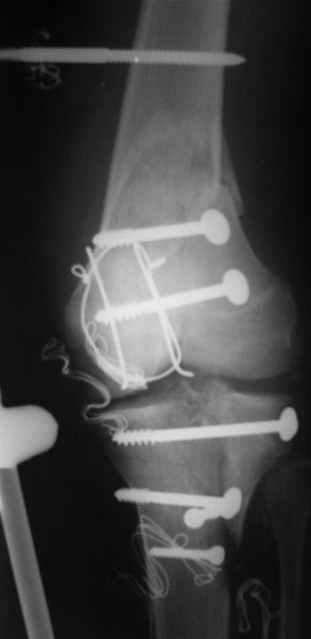

Evgueny Tschekashkin 14 Декабрь 2004, 18:41

Вид раны на сегодня...

4 cутки после травмы.

Спасибо за комментарии. Травма тяжелая с проблематичным прогнозом для функции коленного сустава( изначально травма разгибательного аппарата с последующим частичным некрозом собственной связки надколенника и о обнажением рефиксированного фрагмента бугристости большеберцовой кости, дефектом центрального отдела суставной поверхности большеберцовой кости и медиального отдела капсулы сустава).